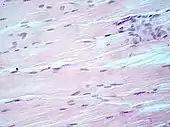

Muscle tissue, cell nuclei (blue-purple), extracellular material (pink).

H&E is the combination of two histological stains: hematoxylin and eosin. The hematoxylin stains cell nuclei a purplish blue, and eosin stains the extracellular matrix and cytoplasm pink, with other structures taking on different shades, hues, and combinations of these colors.[5][6] Hence a pathologist can easily differentiate between the nuclear and cytoplasmic parts of a cell, and additionally, the overall patterns of coloration from the stain show the general layout and distribution of cells and provides a general overview of a tissue sample's structure.[7] Thus, pattern recognition, both by expert humans themselves and by software that aids those experts (in digital pathology), provides histologic information.

Hematoxylin principally colors the nuclei of cells blue or dark-purple,[6][15][14] along with a few other tissues, such as keratohyalin granules and calcified material. Eosin stains the cytoplasm and some other structures including extracellular matrix such as collagen[5][7][14] in up to five shades of pink.[8] The eosinophilic (substances that are stained by eosin)[5] structures are generally composed of intracellular or extracellular proteins. The Lewy bodies and Mallory bodies are examples of eosinophilic structures. Most of the cytoplasm is eosinophilic and is rendered pink.[10][15] Red blood cells are stained intensely red.